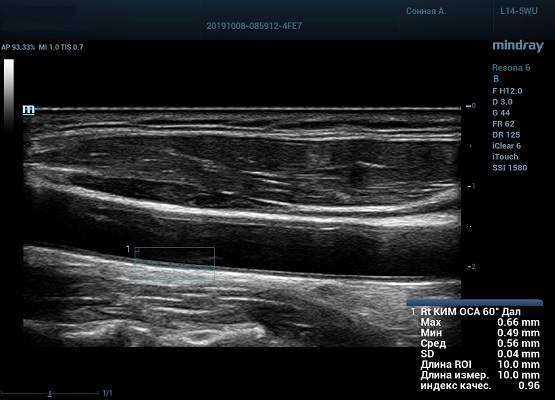

На сегодняшний день измерение IMT происходит автоматическим путем при использовании функции AUTO-IMT. Необходимо указать прибору зону интереса, стандартной длиной (1 см), в которой происходит отслеживание кромок и выдача максимального, среднего и минимального значения. УЗИ аппараты компании Mindray среднего, экспертного и премиального класса снабжены данной функцией и позволяют контролировать не только полученные значения, но и оценить точность измерения кромки в конкретной зоне по индексу качества. Используя индекс качества, легко решить, можно ли использовать полученное значение.